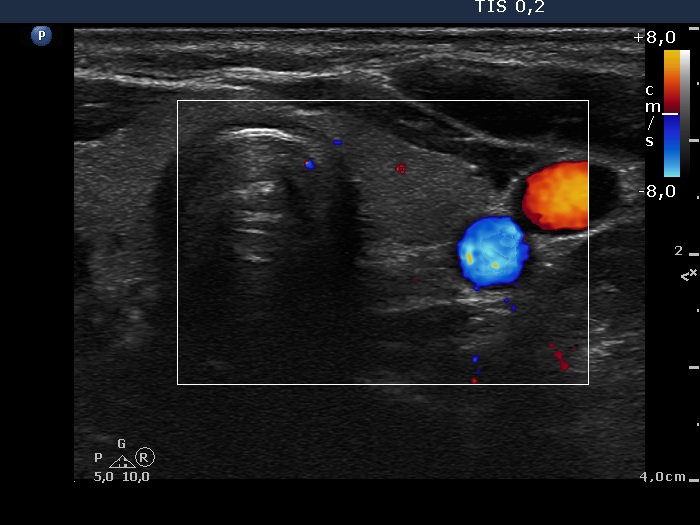

Ultrasonography: The thyroid was echonormal and intact. There was a cystic-minimally hypoechogenic mass lateral and lower to the right thyroid. The vascularization was not specific.